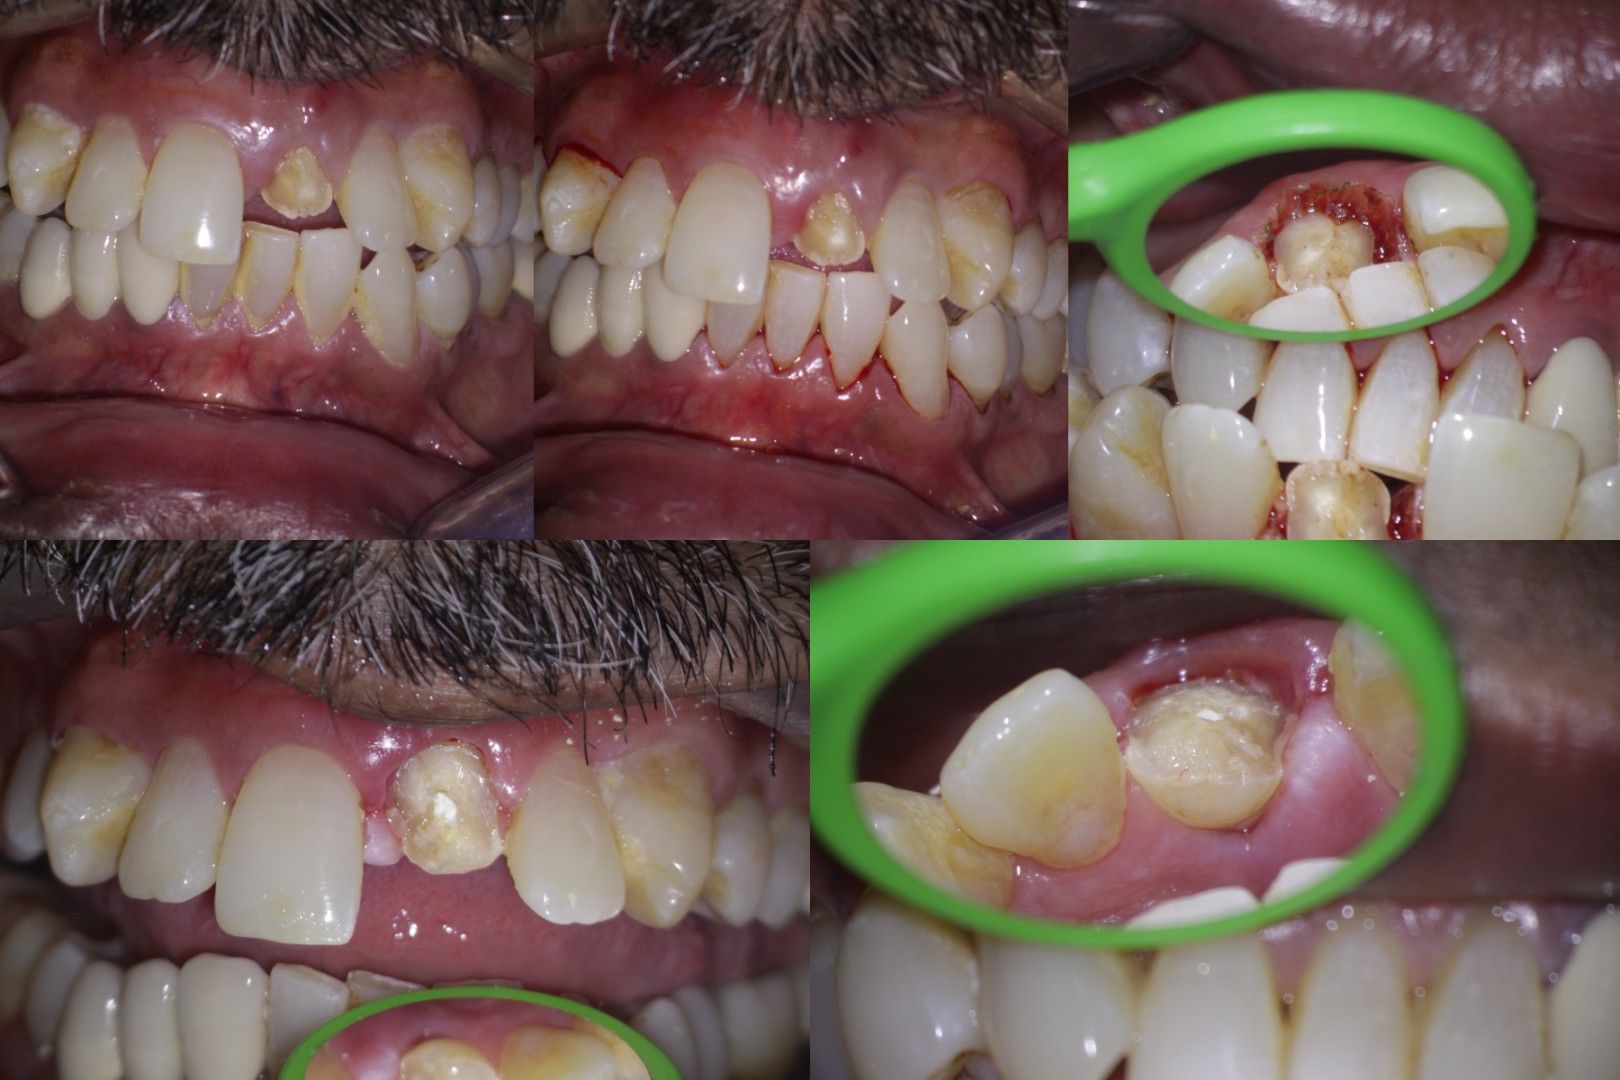

Pt 55 yoM presented with fracture of #9. History of trauma 2 wks back and was aymptomatic. Gingivectomy using electrocautery was done. Root canal therapy was completed after intermittent CAOH dressing , fibre post cemented and composite build up was done.